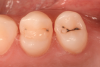

The placement of posterior restorations may lead to postoperative sensitivity.19 Two main characteristics that are important to consider when dealing with posterior restorations are the configuration factor (C-factor) of the preparation and the amount of dentin involved when compared with the amount of enamel. A preparation's C-factor refers to the ratio of bonded to unbonded surfaces. For example, Class I preparations have a C-factor of 5, and Class II preparations have a C-factor of 2. For preparations in which the amount of dentin is greater than the amount of enamel, a self-etch approach is advised because it may reduce postoperative sensitivity. Universal adhesives with functional monomers are able to chemically bond to dentin, which exists in greater amounts in posterior teeth.20 Using them in a selective enamel etching approach can improve the marginal seal that is obtained. In the clinical case described here, two premolars were restored using a universal adhesive in a selective enamel etching approach. The patient presented with primary and a secondary caries on teeth Nos. 12 and 13 (Figure 1). After isolation with a rubber dam (Figure 2), the teeth were prepared using a cylindrical bur, and the enamel was selectively etched with phosphoric acid (Figure 3). A universal adhesive was then applied, and composite was placed to restore the tooth using a cusp-by-cusp modeling approach (Figure 4 and Figure 5).

(1.) Pretreatment photograph of primary and a secondary caries on teeth Nos. 12 and 13.

Figure 1